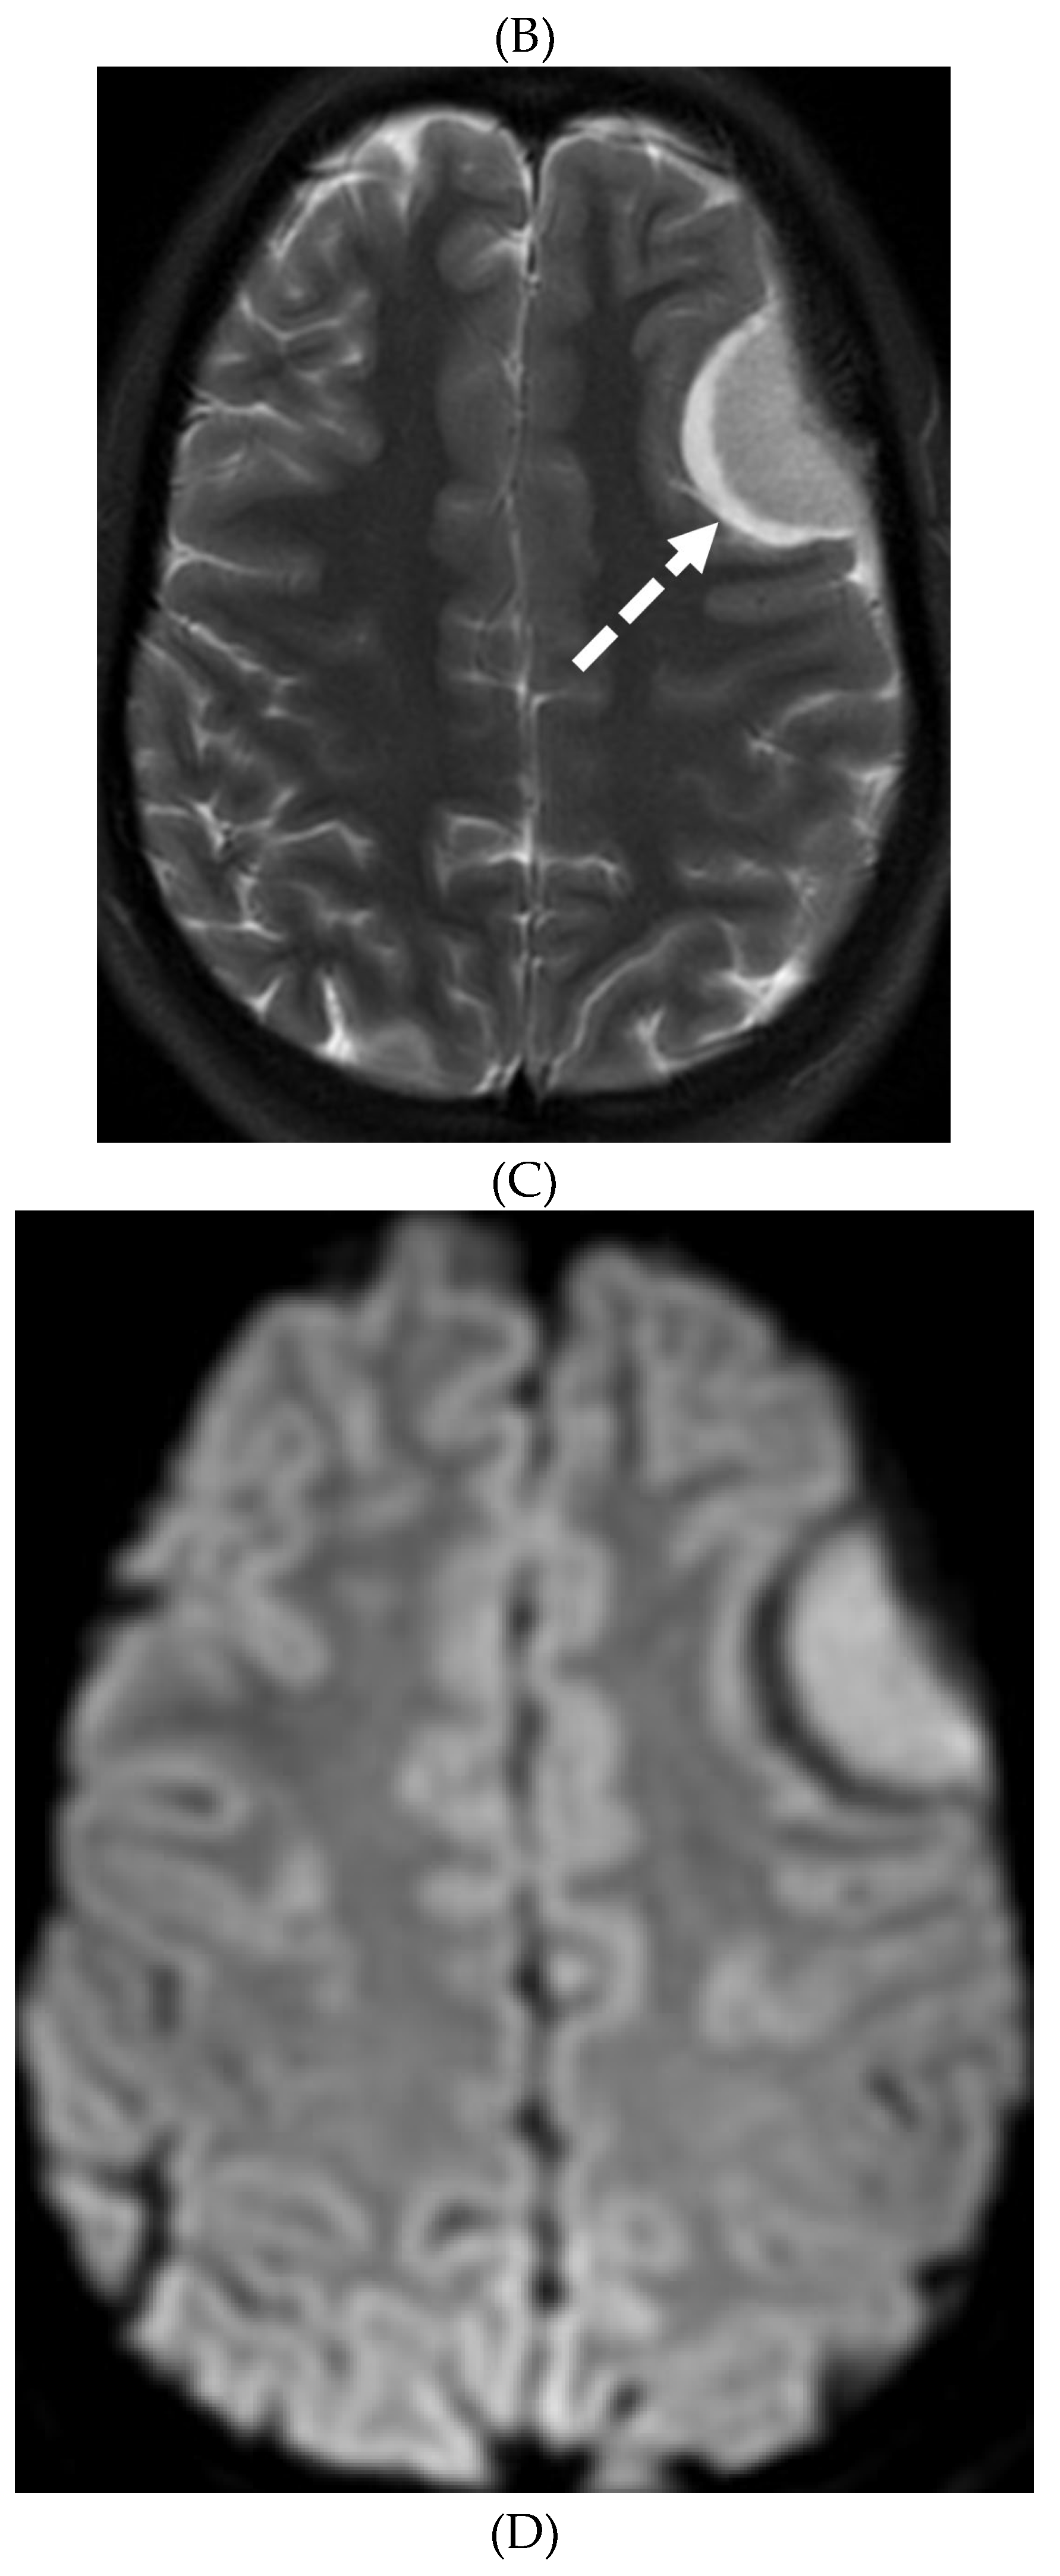

- Liu ZW, Han C, Zhao F, Qiao PG, Wang H, Bao XY, Zhang ZS, Yang WZ, Li DS, Duan L. Collateral Circulation in Moyamoya Disease: A New Grading System. Stroke. 2019 Oct;50(10):2708-2715. Epub 2019 Aug 14. PMID: 31409266. [CrossRef]

- Horie N, Morikawa M, Nozaki A, Hayashi K, Suyama K, Nagata I. "Brush Sign" on susceptibility-weighted MR imaging indicates the severity of moyamoya disease. AJNR Am J Neuroradiol. 2011 Oct;32(9):1697-702. Epub 2011 Jul 28. PMID: 21799039; PMCID: PMC7965393. [CrossRef]

- Ohta T, Tanaka H, Kuroiwa T. Diffuse leptomeningeal enhancement, "ivy sign," in magnetic resonance images of moyamoya disease in childhood: case report. Neurosurgery. 1995 Nov;37(5):1009-12. PMID: 8559324. [CrossRef]

- Maeda M, Tsuchida C. "Ivy sign" on fluid-attenuated inversion-recovery images in childhood moyamoya disease. AJNR Am J Neuroradiol. 1999 Nov-Dec;20(10):1836-8. PMID: 10588105; PMCID: PMC7657767.